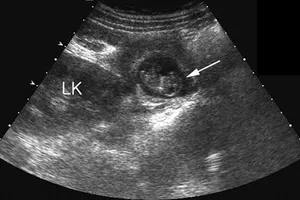

Ca thông van tim bào thai cực khó tại Việt Nam: Một sinh linh được cứu, một kỳ tích được viết nên 30/05/2025 15:35